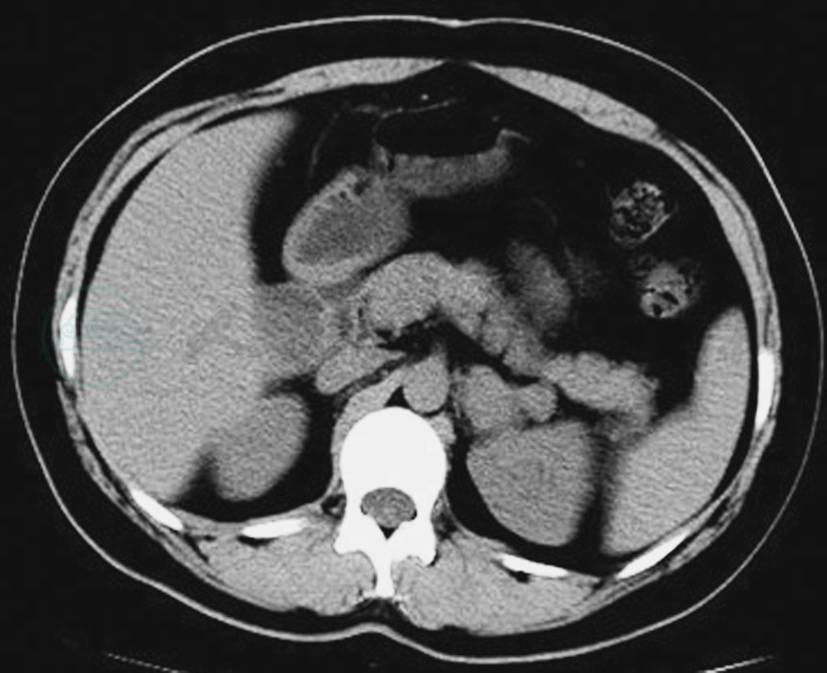

图4左侧肾上腺良性嗜铬细胞瘤

CT平扫示左侧肾上腺瘤体,形态不规则,呈葫芦状